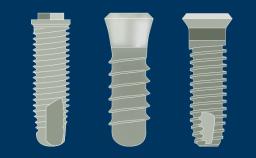

A geometria do corpo dos implantes geralmente pode ser dividida em três partes: a parte endóssea, que se encontra dentro do osso, a seção transmucosa, que fica nos tecidos moles entre o osso e a cavidade oral, e a interface com os componentes protéticos. Em cada uma dessas três partes, existem outras características da geometria e variações na sua forma, atributos e dimensões. Existem também variações no material do corpo do implante e no tratamento de superfície. Essas variações serão descritas e discutidas nos seguintes Objetivos de Aprendizagem.

- descrever as variações na parte endóssea do implante

- descrever as variações nos materiais do corpo do implante e seus tratamentos de superfície